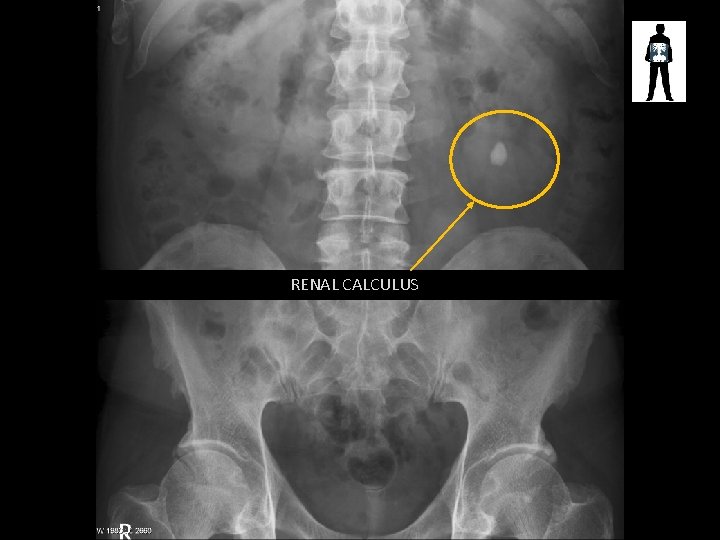

RENAL CALCULUS

STONES! • Cause pain and obstruction of renal/biliary systems – Can be treated by surgical removal or laser fragmentation, lithotripsy or if small enough just monitored until they pass • Patients may undergo fluoroscopic procedures to treat these stones – ERCP – Retrograde Ureterogram – etc